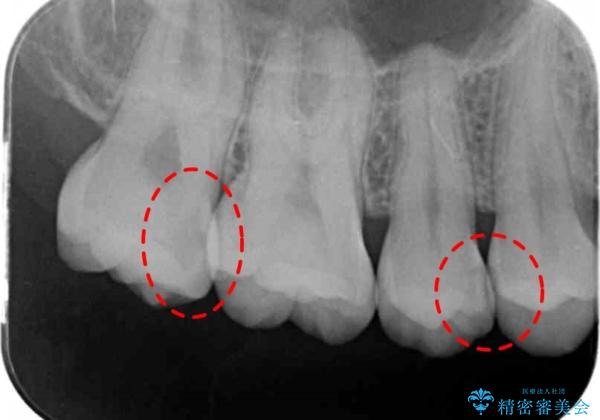

- 検査の結果左上の歯と歯の間に虫歯が発見された患者様です。

虫歯の除去後セラミックインレーでの修復処置をしていきます。

歯と歯の間は虫歯の好発部位とされています。

適合の良いインレーでの修復をすることで再発を防止します。